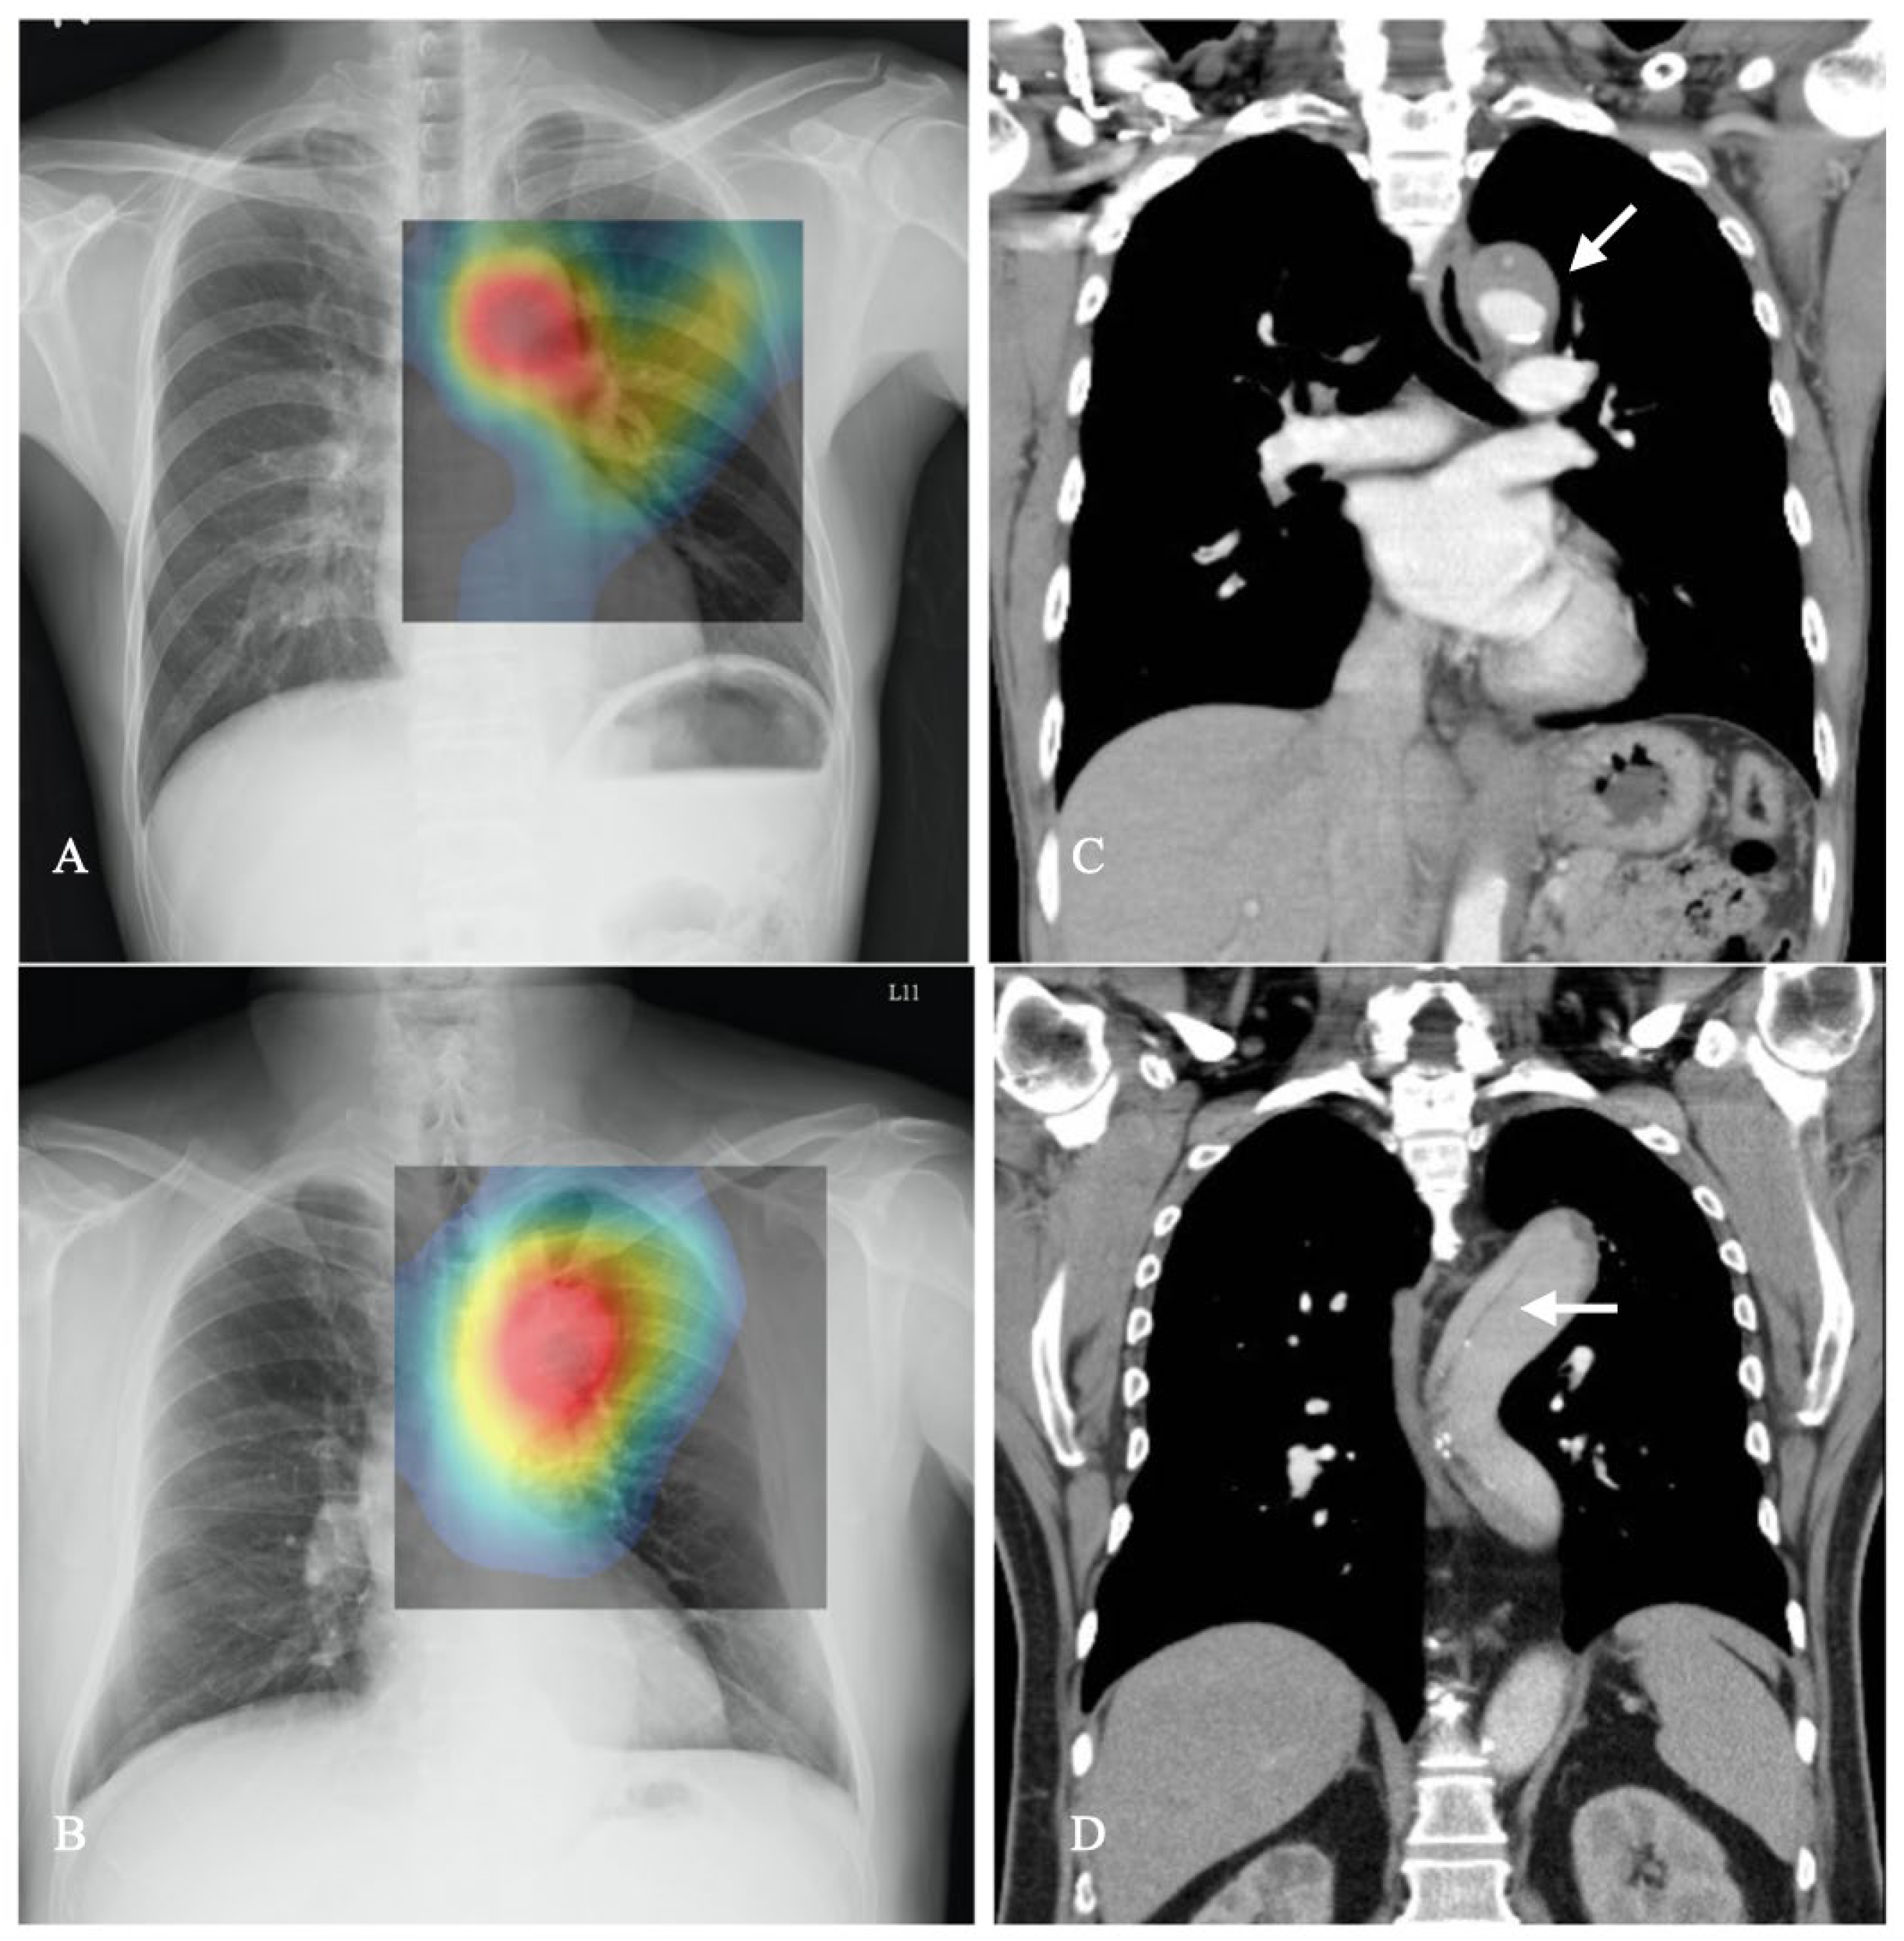

- By incorporating class activation mapping (CAM) in CXRs and comparing it with CTA, our study demonstrates that CNNs have the potential to accurately pinpoint aortic lesions.